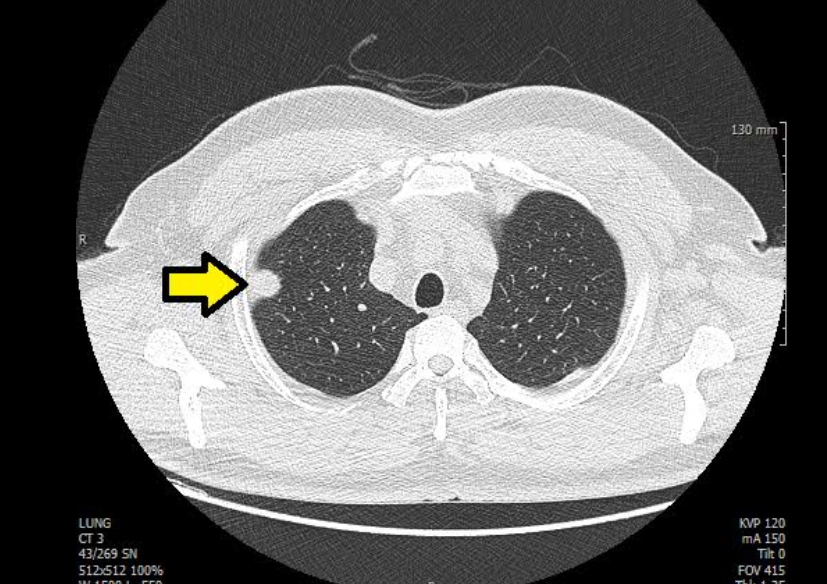

흉부 엑스레이 폐암

폐암은 초기에 특별한 증상이 거의 없어서 조기 발견이 어렵습니다. 흉부 엑스레이는 폐암을 찾아내는 첫 번째 단계로 사용돼요. 작은 혹이나 결절이 보이면 추가로 저선량 CT(방사선량이 적은 컴퓨터 단층촬영)를 진행하게 되죠.

하지만 엑스레이만으로 모든 폐암을 잡아내긴 어려워요. 종양이 아주 작거나 혈관 뒤쪽에 숨어 있으면 안 보일 수도 있습니다. 그래서 흡연력이 있거나 가족력이 있는 분들은 1년에 한 번 정도 저선량 CT를 병행하는 게 좋아요. 저희 아버지도 금연 후 매년 CT를 찍고 계신데, “한 번 찍으면 마음이 편하다” 하시더라고요. 그 말이 참 와닿았어요. 예방이 곧 안심이니까요.